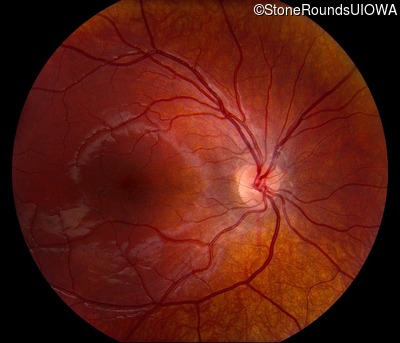

This 6 year old boy first experienced difficulty reading and seeing the blackboard at age 5.

| Age at visit: 6 years |

| Age at visit: 11 years |

| Age at visit: 14 years |

| Age at visit: 14 years (Visit 2) |